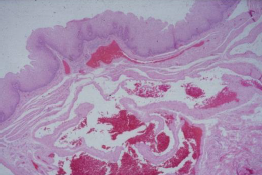

Pathology?

cholesterosis aka strawberry gallbladder accumulation of cholesterol esters and triglycerides in macrophages within lamina propria